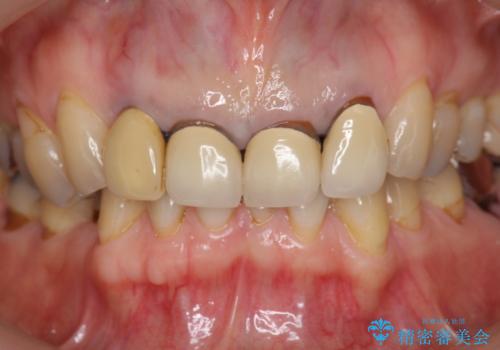

境目の見える前歯をきれいにしたい セラミック治療

- 以前治療した前歯のセラミックの歯ぐきの位置がかわってしまい境目の変色の改善を希望して来院されました。

大きな穿孔が見られた、右上側切歯の抜去をこないブリッジの設計を含めた前歯の審美性の改善を目的とするセラミック治療を行いました。